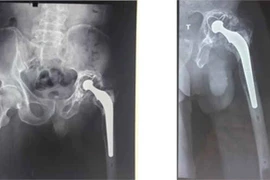

Sau hơn 4,5 giờ căng thẳng đục xi măng, bỏ khớp hư, các bác sĩ Bệnh viện T.Ư Quân đội 108 đã thành công thay được khớp mới có chuôi dài 36cm cho một ca bệnh vô cùng khó và phức tạp.